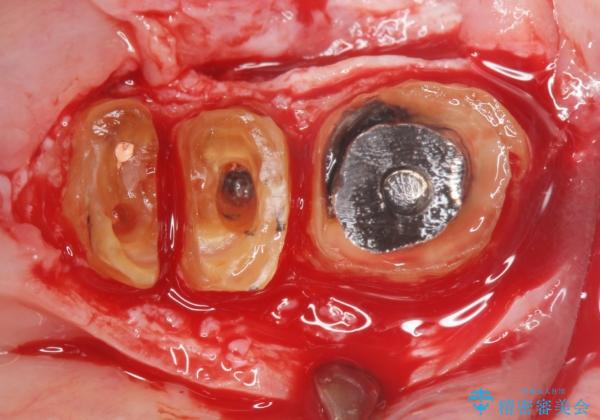

虫歯を丁寧に除去した後に歯根を分割し、骨を削合して健全歯質を露出させる骨外科手術を行いました。

手術後に根管治療を行い、歯肉と骨の治癒を十分に待った後ブリッジによる補綴治療を行いました。